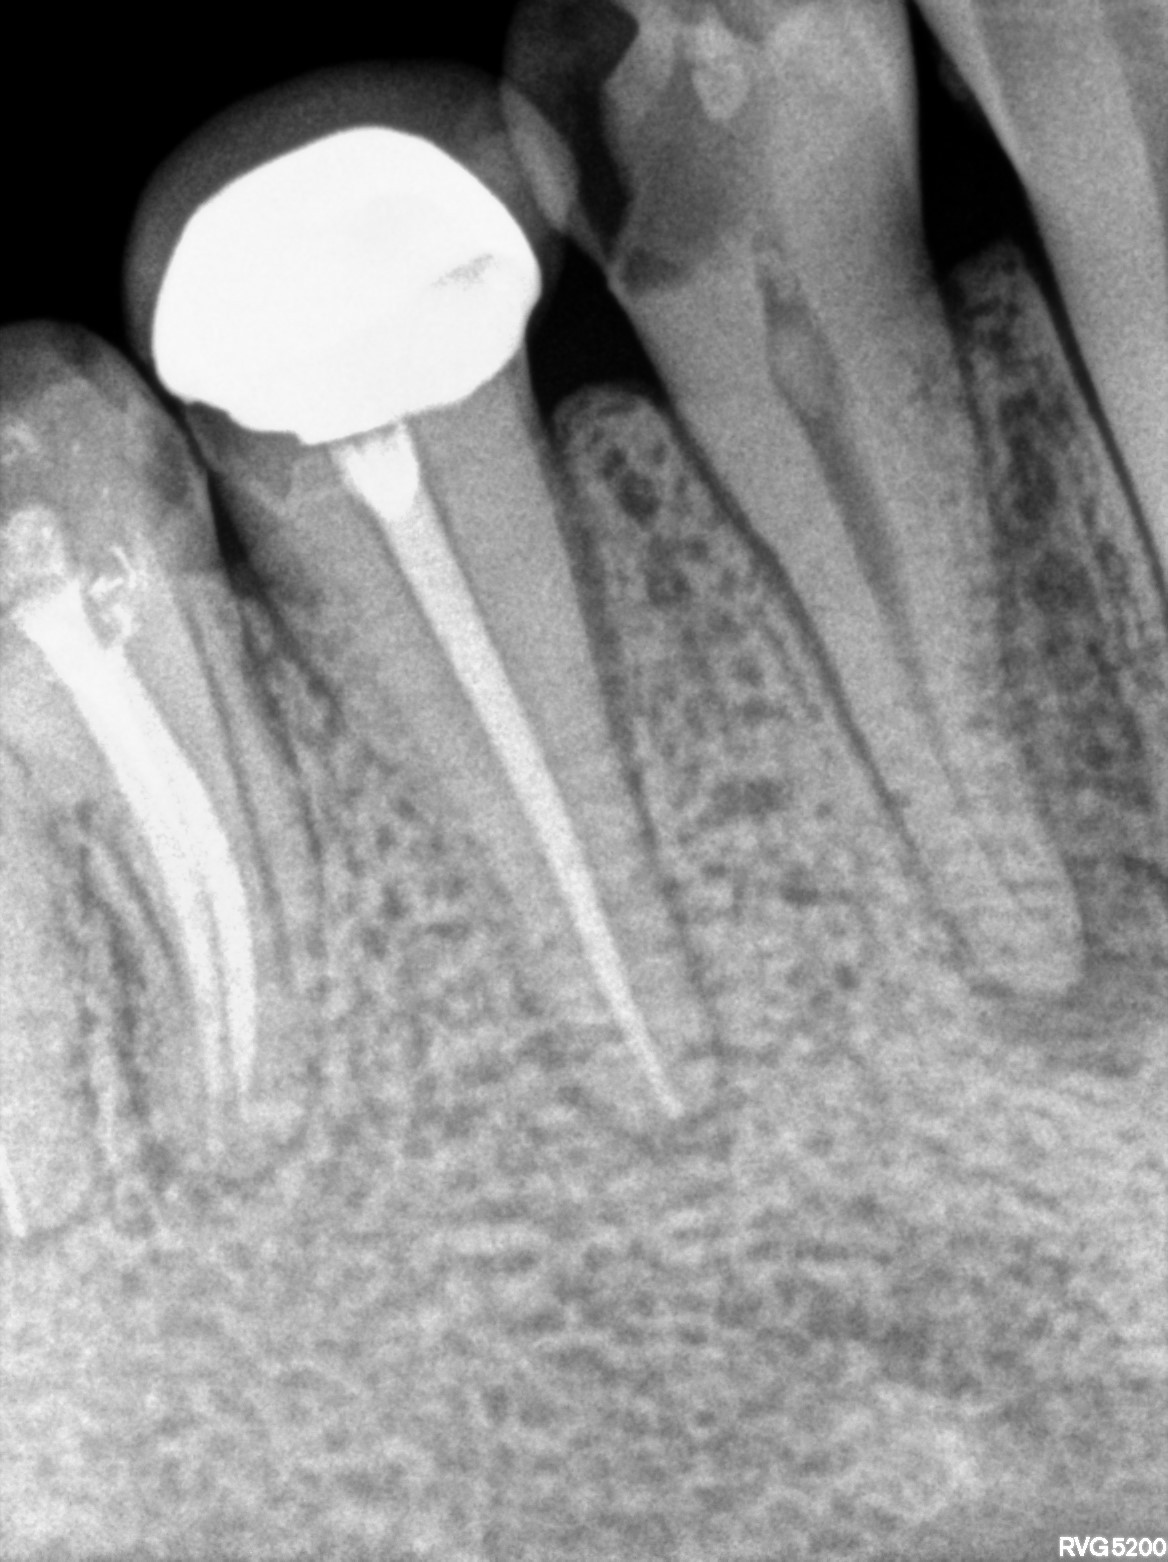

Dental Radiographs FHIR: DocumentReference · LOINC 24641-7

xray_1770308600_0.jpg

24641-7

| Root canal treatment | 234780006 | D3320 Endodontic therapy, premolar tooth | ##35 | 2024-09-17 | completed | a/o with 35 & bmp-30-06 & hypo done | |

| 2024-09-17 13:03 | fulfilled | a/o with 35 & bmp-30-06 & hypo done — NULL | |